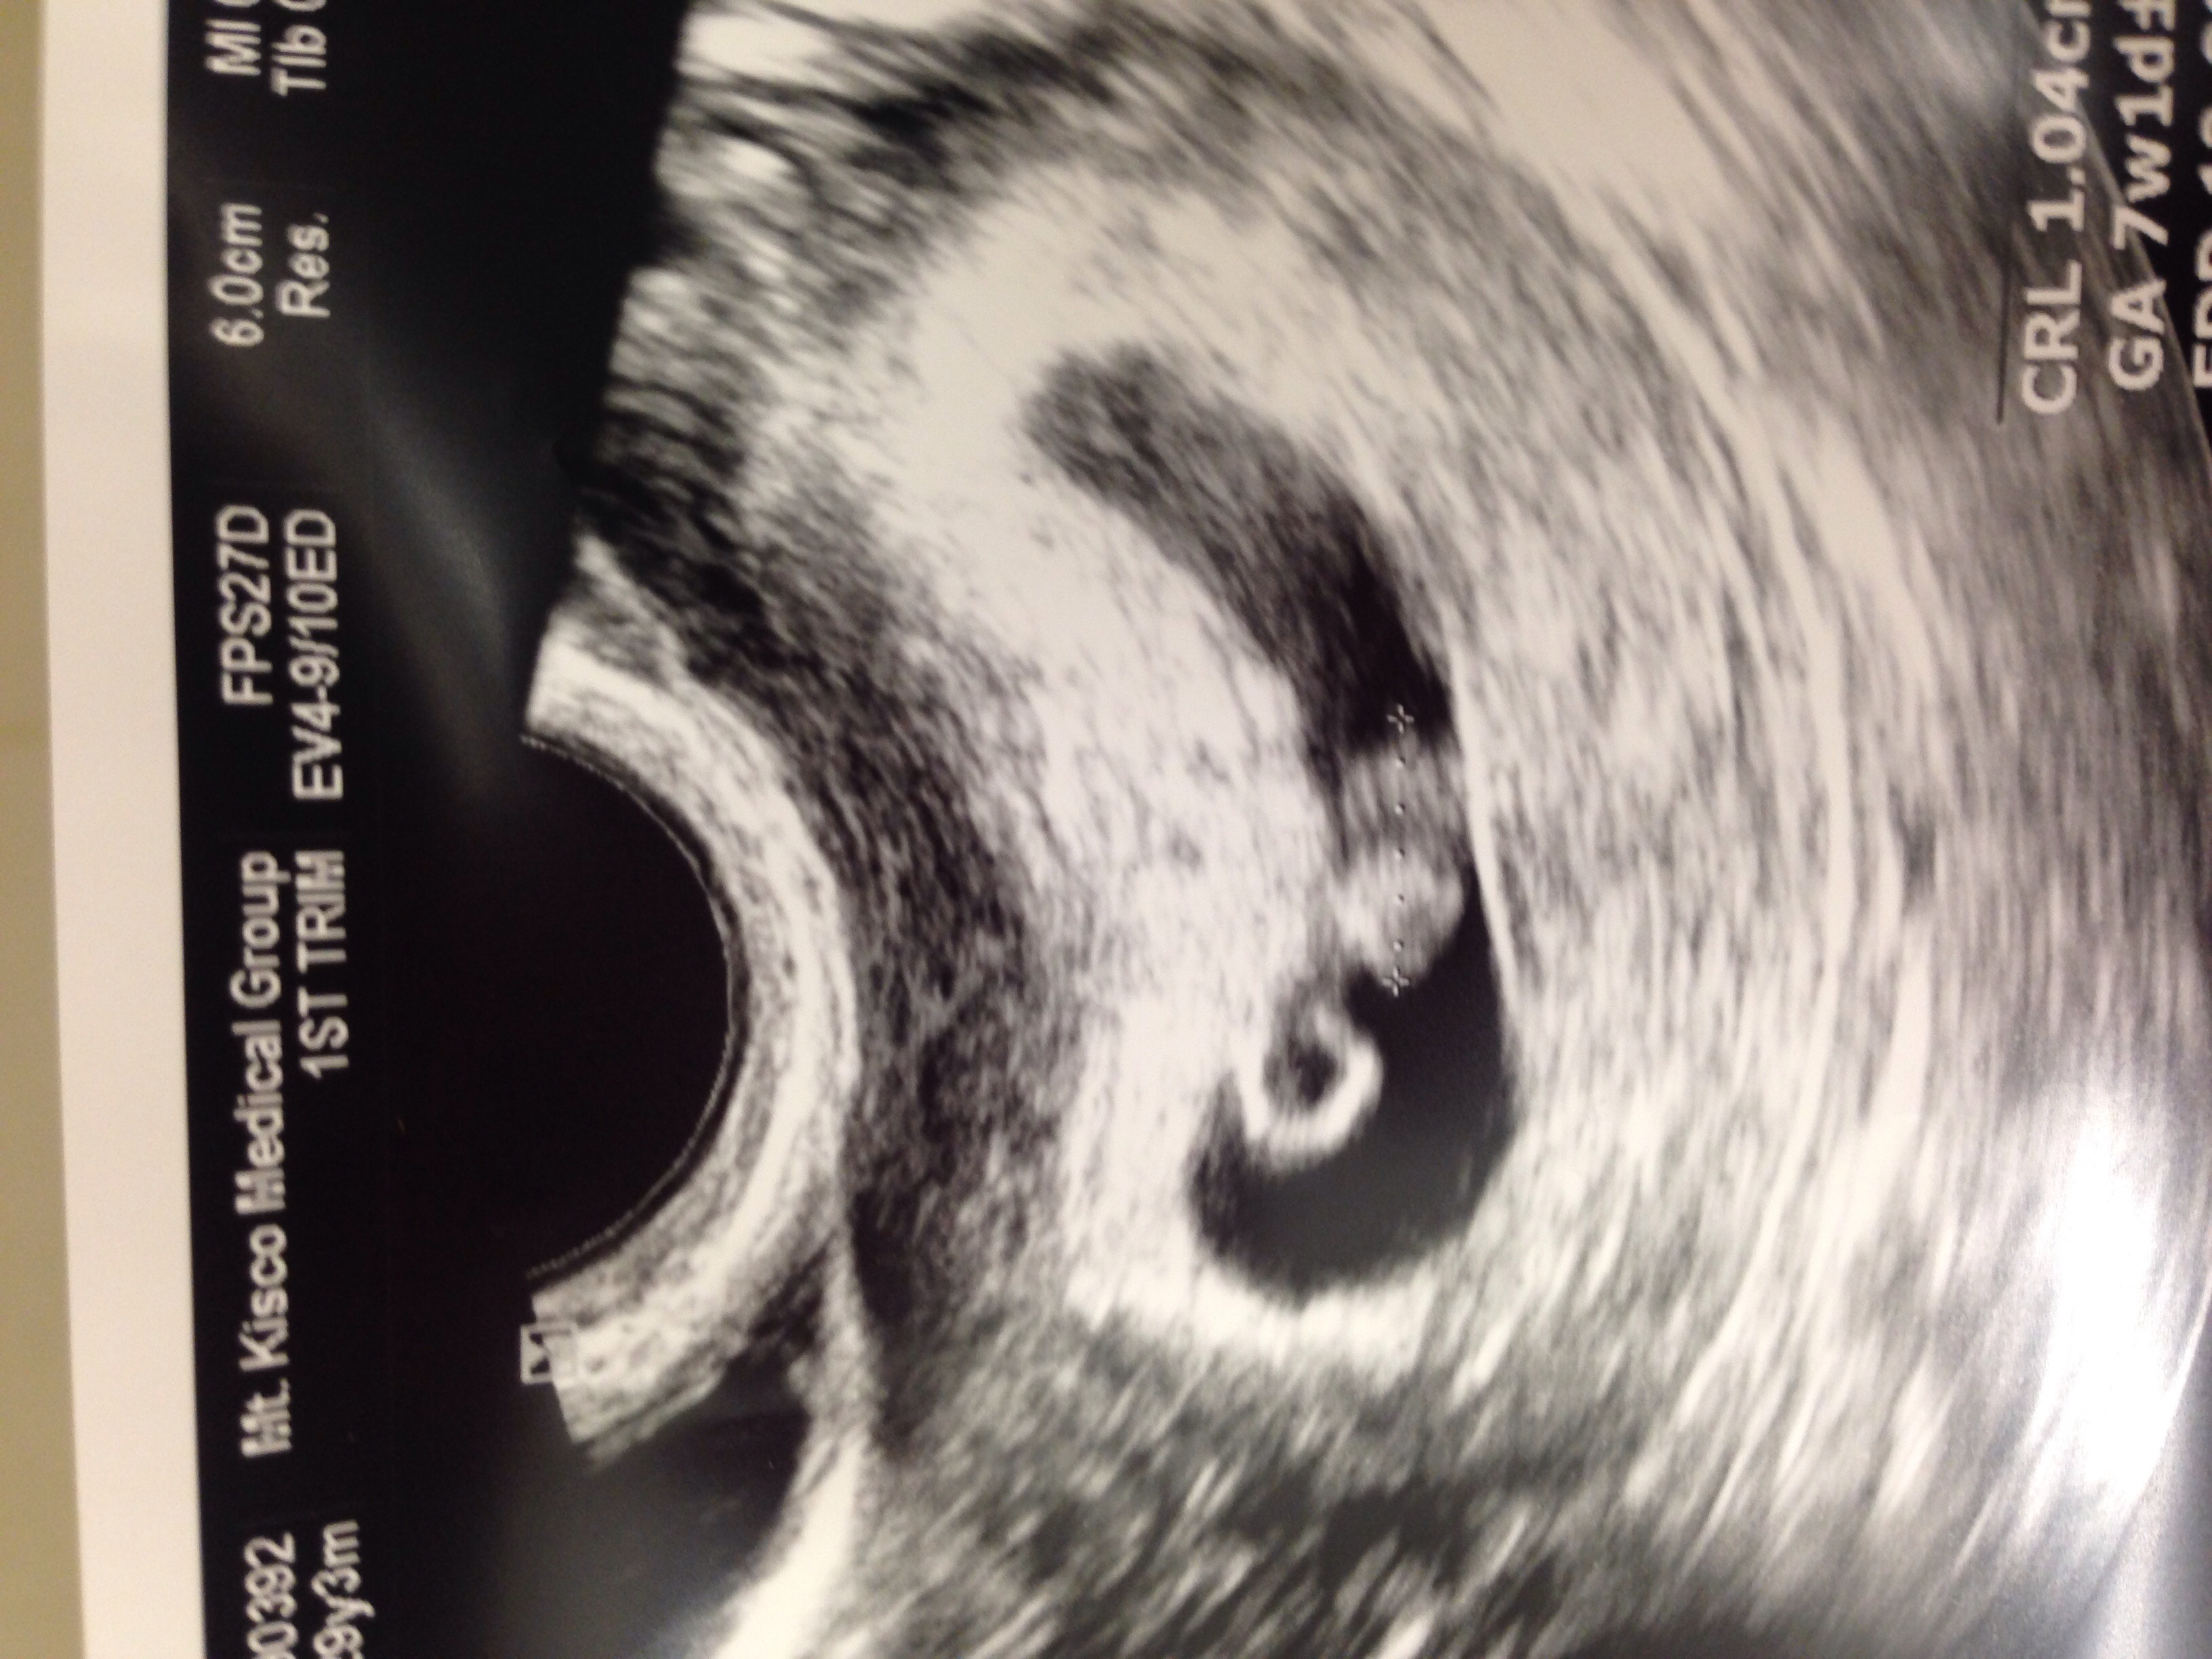

Our little peanut measured 7 weeks 1 day- a few days off, so our new due date is Dec 30. I am still a December birth month yay! Good heartbeat, very relieved and excited!